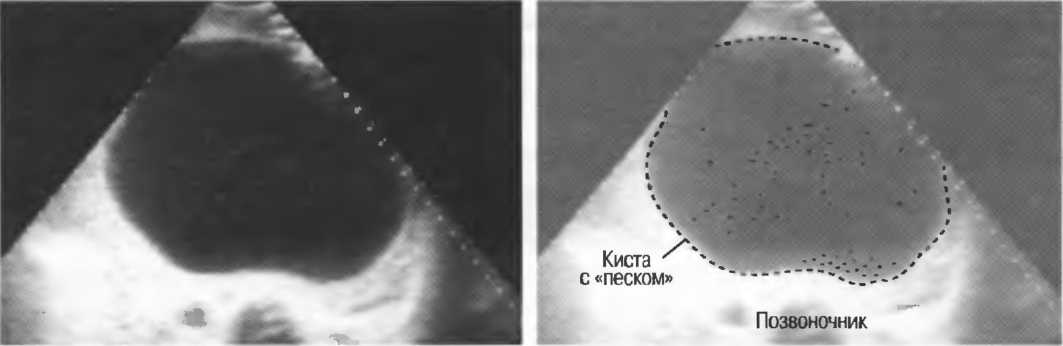

Кисты

Киста, как правило, визуализируется в виде анэхогенной зоны, при этом структуры, расположенные за кистой, обычно усилены: полость кисты анэхогенна, поскольку в ней нет структур с различным акустическим сопротивлением. В результате того что жидкость не поглощает ультразвук в такой же степени, что и ткань, эхо-сигналы от расположенных позади кисты структур гиперкомпенсированы сканером и выглядят усиленными — появляется эффект усиления задней стенки (рис. 14а,б).

Киста определяется в виде анэхогенной зоны с усилением по задней стенке. Если в кисте есть внутренние зхоструктуры, то они могут быть реальными или являться артефактами.

Рис. 14а. Заполненная жидкостью киста: полость кисты анзхогенна, имеется усиление задней стенки.

Рис.14б. Данная киста яичника имеет толстые стенки и внутренний осадок, создающий внутреннюю эхоструктуру, перемещающуюся при перемене положения тела пациента.

Если уровень чувствительности прибора достаточно низок, солидное образование может выглядеть кистозным. Но при этом нет усиления задней стенки (нет дорсального усиления).

Если уровень чувствительности прибора слишком высок, жидкостные структуры могут иметь внутренние зхоструктуры и выглядеть солидными.